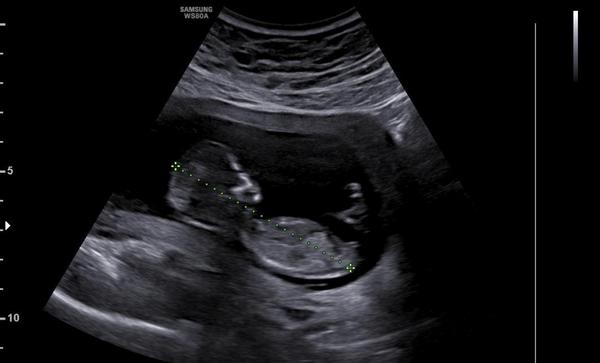

Pokud jsem správně pochopila, pokud je na ultrazvuku vidět výběžek, který směřuje nahoru, pak je to chlapec, pokud je ve vodorovném směru s tělem, pak je to pravděpodobně holčička.

Já podle svého už však nevím, zda se jedná o tento výběžek nebo jestli je to třeba nožička... :D Nemáte někdo zkušenost? 🙂 Určitě nečekám diagnózu, jen by mě zajímala Vaše zkušenost a zda jste na svém ultrazvuku neviděly třeba něco podobného. 🙂

Já bych podle toho svého tipla, ze by to mohla být holčička, ale třeba je to jen mé vymodlené přání. :D

Jsem nedočkavá, až se to u svého doktora dozvím 😍 můj screening pro zajímavost v příloze, máte tip? Za